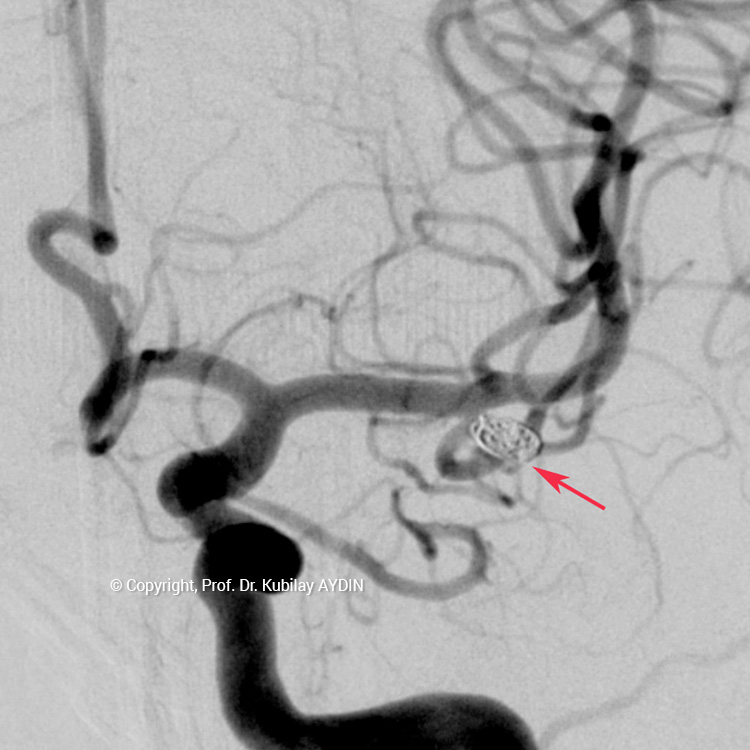

Tüm kapalı anevrizma tedavileri, hasta genel anestezi ile uyutularak gerçekleştirilir. Kapalı anevrizma tedavisinin tüm aşamaları, bacak atardamarı içine yerleştirilen 2 mm çaplı (kurşun kalemden daha ince) bir özel kateter yoluyla uygulanır. Bu küçük giriş noktasından damar içine çok ince (0.5mm çapında) ve yumuşak yapıda mikrokateter adını verdiğimiz özel plastik tüp gönderilir. Anevrizmayı kapatmak için kullandığımız bu mikrokateter, anjiografi cihazında izlenerek anevrizmanın bulunduğu damar içine yönlendirilir. İçi boş, çok ince ve yumuşak bir plastik tüp şeklinde olan mikrokateterin ucu, anevrizma kesesi içine yerleştirilir. Daha sonra bu mikrokateter içerisinden gönderilen platinden yapılmış çok yumuşak “koil” adı verilen tellerle anevrizma kesesi doldurulur. Koiller, anevrizma kesesi içinde bir yumak oluşturup, anevrizma içine kan girişini engeller. Anevrizma kesesi, koillerle tamamen doldurulup, anevrizma içine kan girişi tam olarak durduğu zaman, mikrokateter anevrizma içinden geri alınarak işlem tamamlanır. Anevrizmanın koil adı verilen özel tellerle doldurularak kapatılma işlemine, "koilleme" adı verilir. Anevrizmanın koillenerek kapatılması işlemi, oldukça güvenli ve etkili bir tedavi yöntemidir. Kanamamış beyin anevrizması olan hasta, koilleme yöntemi ile tedavi edildikten 1-2 gün sonra hasta normal günlük yaşamına dönebilir.